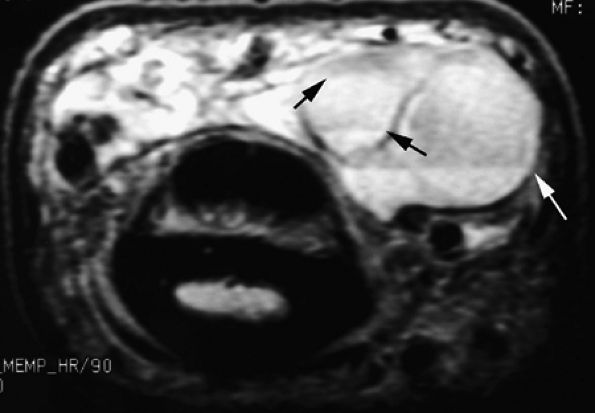

Venous malformations are isointense on T1-weighted sequences and hyperintense on T2-weighted sequences.177 The high T2 signal is related to increased free water within blood pools in the venous malformation.

Signal intensity is often heterogeneous and areas of low signal, caused by fibrous septa, calcifications, thrombi, or hemosiderin deposition after thrombosis, may be seen on T2-weighted images.171,178

Phleboliths present as low-signal-intensity punctuate areas on both T1- and T2-weighted images.

Areas of high signal on T1-weighted images may be related to thrombi (see Fig. 11.76).

Articular, cartilaginous, or osseous invasion may also be depicted on MR studies (Fig. 11.77).

MR imaging is particularly useful in displaying the relationship of the venous malformation with adjacent structures, such as muscles, tendons, and nerves.

Venous malformations are frequently multifocal, have both intramuscular and subcutaneous components (see Fig. 11.77), and follow the neurovascular bundles of the affected limb.179